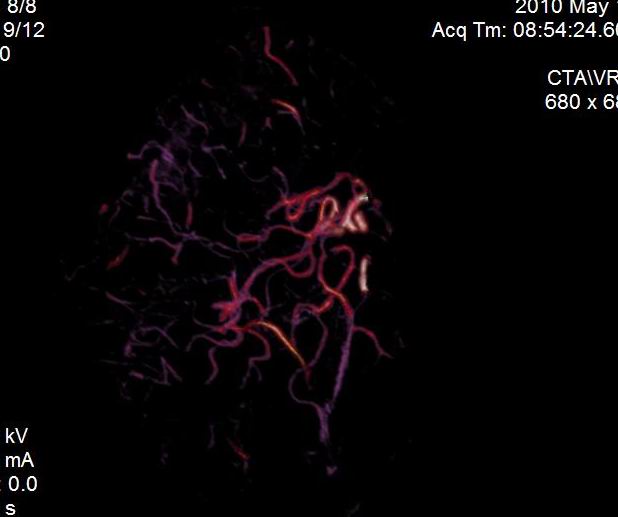

男.60岁,渐进性意识不清,ct检查双侧额颞顶部硬膜下血肿,开颅术后行脑血管cta,大脑中动脉起始部见一瘤状血管扩张。请各位老师留下宝贵意见

太常见了,报动脉瘤就可以

符合动脉瘤表现。

符合动脉瘤表现。

动脉瘤。

颅内动脉瘤。

后重建做得不是很好看,要将维蒂斯环充分显示,最好在增加一个mip。这样不好定位。

小动脉瘤

典型

符合动脉瘤的表现

动脉瘤

符合动脉瘤表现。

小动脉瘤

典型